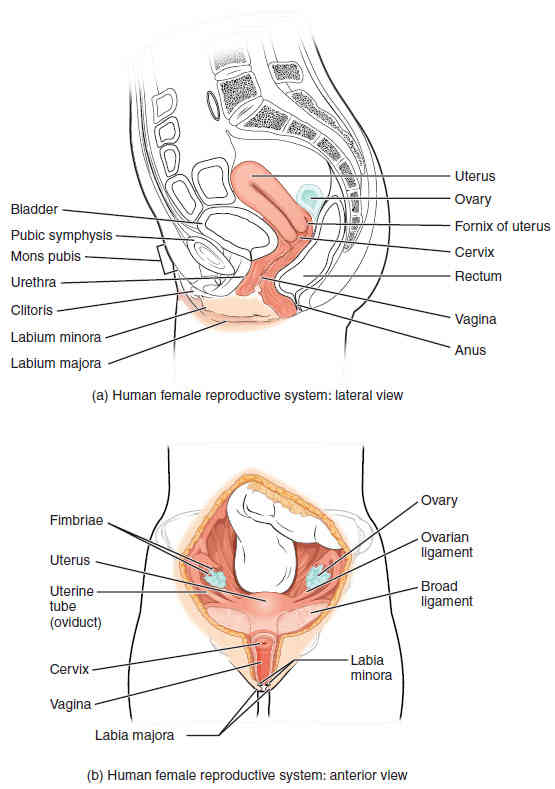

This page is under construction. For now, it is just a resource of the images found in the OpenStax Anatomy and Physiology Handbook. It wil slowly change into a revision tool. Each slide has a number. Use this to refer to the slide. When completed, it will have an unlabelled section, with labelled slides in parallel. On the unlabelled slides, write your answer and use the labelled slide to assess yourself. Keep track by also noting the number on each slide. Improvement at each attempt is important, more so than full marks on a first attempt.